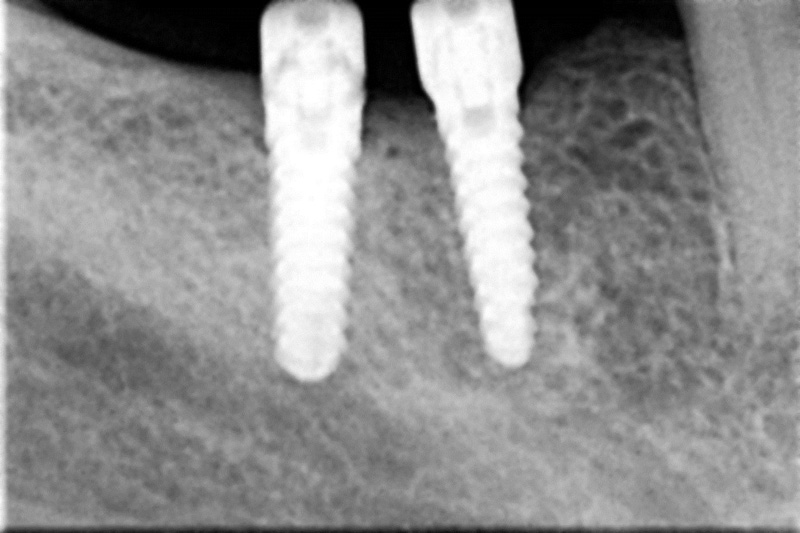

Velká mezera

V případě chybění většího počtu zubů v postranních úsecích čelistí je možné ošetření pomocí implantátů, které nahradí ošetření pomocí snímacích náhrad kotvených na zbývajících zubech nebo patře.

Podmínkou je opět dostatečné množství kosti.

Protetické řešení může být pomocí můstku, který je kotvený na implantátech nebo pomocí jednotlivých korunek na implantátech.

V zásadě je možné do těchto můstků zařadit i přirozené zuby, zejména pokud je potřeba tyto zuby ošetřit proteticky - korunkami. Korunky nebo můstky mohou být na implantáty nacementovány nebo přišroubovány.